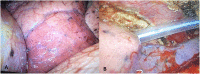

Case presentation: Two patients presented to our hospital with spontaneous pneumothorax associated with Sars-Cov2 infection onset. After initial conservative treatment with chest drain, both patients had a recurrence of pneumothorax during COVI-19 disease, contralateral (patient 1) or ipsilateral (patient 2) and therefore underwent lung surgery with thoracoscopy and bullectomy. Intraoperative findings of COVID-19 pneumonia were parenchymal atelectasis and vascular congestion. Lung tissue was very frail and prone to bleeding. Histological examination showed interstitial infiltration of lymphocytes and plasma cells, as seen in non specific interstitial pneumonia, together with myo-intimal thicknening of vessels with blood extravasation and microthrombi.